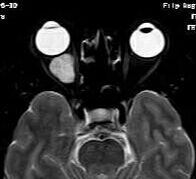

女,54岁,头痛头晕月余,无眼部症状及视力异常。 影像表现:右侧眼球后方占位病变,考虑海绵状血管瘤可能性大,鉴别:视神经鞘瘤、脑膜瘤及炎性假瘤。 病例点评:眼眶内血管瘤是较常见的良性肿瘤,其中以海绵状血管瘤最常见。可发生于任何年龄,主要表现为眼球突出及偏位,在低头或哭泣时可有突眼加重。可经眶缘触及具有压缩性的肿块。视力损害多较缓慢。肿块大多位于肌锥内,其次为肌锥外,平扫呈边界清楚的圆形、卵圆形或分叶状肿块,增强扫描呈缓慢进行性显著强化为其特征性表现。